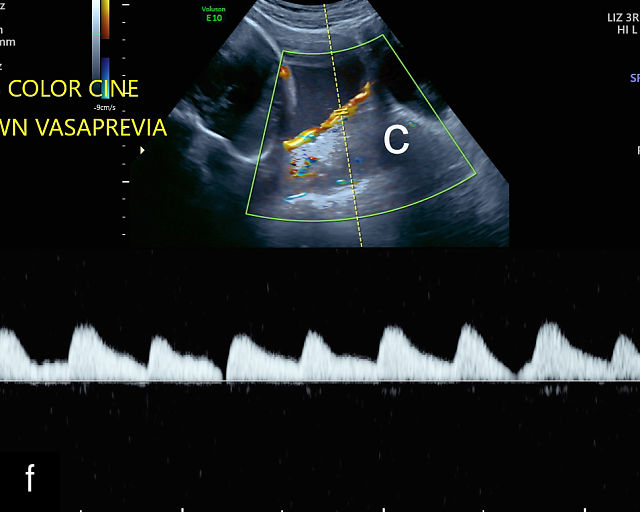

21

(a) Type-1 vasa previa. Photograph after delivery showing the umbilical cord inserting into the membranes through which unprotected fetal vessels run to insert into the placental edge. (b) Type-2 vasa previa. Photograph after delivery showing bilobed placenta with unprotected fetal vessels running though the membranes between the lobes. (c) Type-3 vasa previa in a twin pregnancy. Photograph after delivery showing unprotected vessels running through the membranes from one edge of the placenta to another (arrow). (d) Transabdominal grayscale ultrasound of the lower uterine segment showing a linear hypoechoic structure (fetal vessel) running over the cervix (c) indicating vasa previa (Type 2). b, bladder; h, fetal head. (e) Transabdominal color Doppler ultrasound of the lower uterine segment showing fetal vessels (arrow) running over the cervix (c) indicating vasa previa (Type 2). (f) Transabdominal ultrasound with color flow and pulsed-wave Doppler of the lower uterine segment showing a fetal vessel running over the cervix (c) indicating vasa previa (Type 2). Pulsed-wave Doppler demonstrates an umbilical arterial waveform. (g) Transvaginal grayscale ultrasound with showing a Type-2 vasa previa. There are two placental lobes, an anterior (a) and a posterior (p) lobe. There is a linear and circular hypoechoic structure (arrow) running over the cervix (c) between the lobes. (h) Transvaginal grayscale ultrasound image of vasa previa. A hypoechoic linear structure (arrow) is seen running through the membranes over the cervix (c). h, fetal head. (i) Transvaginal grayscale ultrasound of vasa previa. Hypoechoic circular and linear structures are seen close to the internal os. (j) Transvaginal color Doppler ultrasound image of vasa previa. A fetal vessel is seen running through the membranes over the internal os (arrow) of the cervix (c). h, fetal head. (k) Transvaginal ultrasound with color Doppler showing a Type-2 vasa previa. There are two placental lobes, an anterior and posterior lobe (pl). Fetal vessels run over the cervix between the lobes. (l) Transvaginal color flow ultrasound with pulsed-wave Doppler image of vasa previa. Color Doppler shows flow through the vessel and pulsed-wave Doppler shows a fetal umbilical venous waveform. (m) Transvaginal color ultrasound with pulsed-wave Doppler image of vasa previa. Color flow Doppler shows flow through the vessel and pulsed-wave Doppler shows a fetal umbilical arterial waveform. (n) Transvaginal three-dimensional ultrasound with color Doppler image of vasa previa. h, fetal head; c, cervix.

12

Transvaginal ultrasound imaging of Type-1 vasa previa. Color Doppler (a,c,d) and grayscale (b) imaging shows fetal vessels running over the cervix.

In all pregnancies, the placental cord insertion should be identified at the time of the second-trimester anatomy scan. In addition, a color flow Doppler sweep of the region overlying the cervix should be performed. The ultrasound appearance of vasa previa is of hypoechoic linear or circular structures overlying or in close proximity to the internal os (Figure 21).30,187,252,263 When these are observed, color flow Doppler should be employed to confirm flow through these structures.30,187 Transvaginal ultrasound with color and pulsed-wave Doppler is essential for diagnosing vasa previa; the presence of a fetal arterial or venous waveform on pulsed-wave Doppler confirms the diagnosis (Figure 21). A common misconception is that vasa previa occurs only when a fetal artery overlies the cervix; however, a fetal vein overlying the cervix also constitutes vasa previa (Figure 21l).265 The precise distance of fetal vessels from the internal os required to define vasa previa has been debated.266 While some have used a distance of 2 cm, others argue that unprotected fetal vessels within 5 cm of the internal os are at risk of rupture, particularly given that the cervix dilates to 10 cm during labor. Some experts advocate for a 5-cm threshold to define vasa previa.266,267 An international Delphi consensus of vasa previa experts recommended that the definition should not be limited to a 2 cm cutoff, acknowledging the variability in clinical practice.268

Transvaginal ultrasound with color flow Doppler is highly accurate in the diagnosis of vasa previa, with a systematic review and meta-analysis finding sensitivity and specificity of greater than 99%.269

False positives may arise due to several factors, including funic presentation (where free loops of the cord overlie the cervix), movement artifacts on color Doppler, placenta previa or maternal vessels.30,263 Free loops of the umbilical cord typically move away from the cervix with changes in maternal position and do not persist on serial ultrasound examinations.187

When vasa previa is suspected during the second trimester, transvaginal sonography with color Doppler should be repeated at around 32 weeks to confirm the diagnosis. This follow-up is essential, as 15–40% of vasa previa cases identified in the second trimester resolve spontaneously before delivery.270,271 It is also critical to ensure that the fetal head is not engaged, as this can compress and obscure fetal vessels, potentially leading to a false-negative diagnosis.272 In such cases, manual elevation of the fetal head may be necessary, but care must be taken to avoid compressing the vessels during this maneuver, as it can also result in a missed diagnosis.273